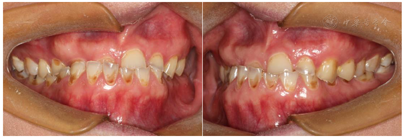

(1)面部检查:面部外形不对称,颏部居中,两侧口角高度不一致,面下1/3高度减小,两侧颧弓突度一致,下颌前突。中位笑线,上唇长度适中(图1)。(2)关节检查:颞颌关节:弹响(-),杂音(-),疼痛(-)。开口度正常,开口型有偏斜,肌肉触诊压痛:右侧上颌结节(+)、左侧上颌结节(++)、双侧翼内肌(+),其他肌肉及颞下颌关节区未诉异常,关节载荷实验无任何紧张和疼痛不适。(3)口内检查:上下颌牙中线较面中线向右偏斜,前后牙广泛不均匀磨耗,前牙磨耗后呈刃状;14、21、22、23及下颌牙唇颊侧颈部见釉质缺损,部分牙本质暴露,呈黄褐色,少量白垩色;44牙见开髓孔,表面暂封。12缺失,缺失牙间隙无。全口牙龈色形质未见异常,11牙、21牙唇侧牙龈龈缘高度不一致,21牙较11牙龈缘高约3mm。全口口腔卫生状况良好,菌斑、软垢少量,未及牙石及牙周袋。咬合检查:11-14牙与对颌牙反

,21牙与31、31牙对刃,左侧尖牙至前磨牙深覆盖,

曲线不平(图2,图3)。(4)影像学检查: